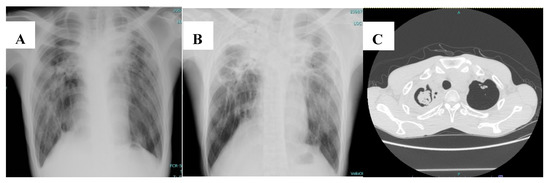

Common radiological findings that increase the possibility of CPA in NTM-infected patients include thickening of pre-existing lung cavities, the presence of a fungal ball, and infiltration surrounding the cavities [30]. To better illustrate this, Figure 1 shows the chest imaging of a patient who was diagnosed with CPA following pulmonary NTM disease caused by M. avium.

Figure 1.

Chest imaging of a 37-year-old man diagnosed with chronic pulmonary aspergillosis following pulmonary Mycobacterium avium infection. (A) Chest radiograph showed cavitary lesion at right upper lobe (pulmonary Mycobacterium avium infection). (B) Chest radiograph 1 year later showed thickening of pre-existing cavities, with pericavitary infiltration (chronic pulmonary aspergillosis). (C) Computed tomography of the chest showed a fungal ball in the pre-existing cavity.